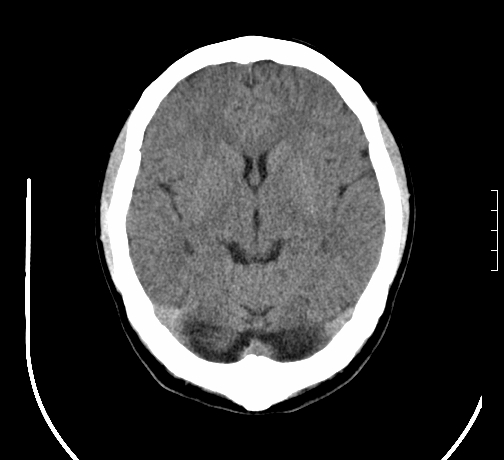

女,28岁,幼时有癫痫,常有发作,服药后可几月不发作,走路不稳3-4月,加重一月。

小脑发育畸形?

小脑萎缩。

考虑小脑发育不良,建议mri检查。

患者出现走路不稳是近几个月的事,而癫痫则有幼时就有,常发,则会常服药,癫痫药可引起小脑综合症,小脑萎缩,而小脑发育不良的主要症状不是癫痫

考虑癫痫,长期间断发服抗癫药,导致小脑综合症,小脑萎缩

考虑小脑发育不良伴小脑萎缩,建议mri检查。

小脑萎缩,原因待查,建议mri检查。